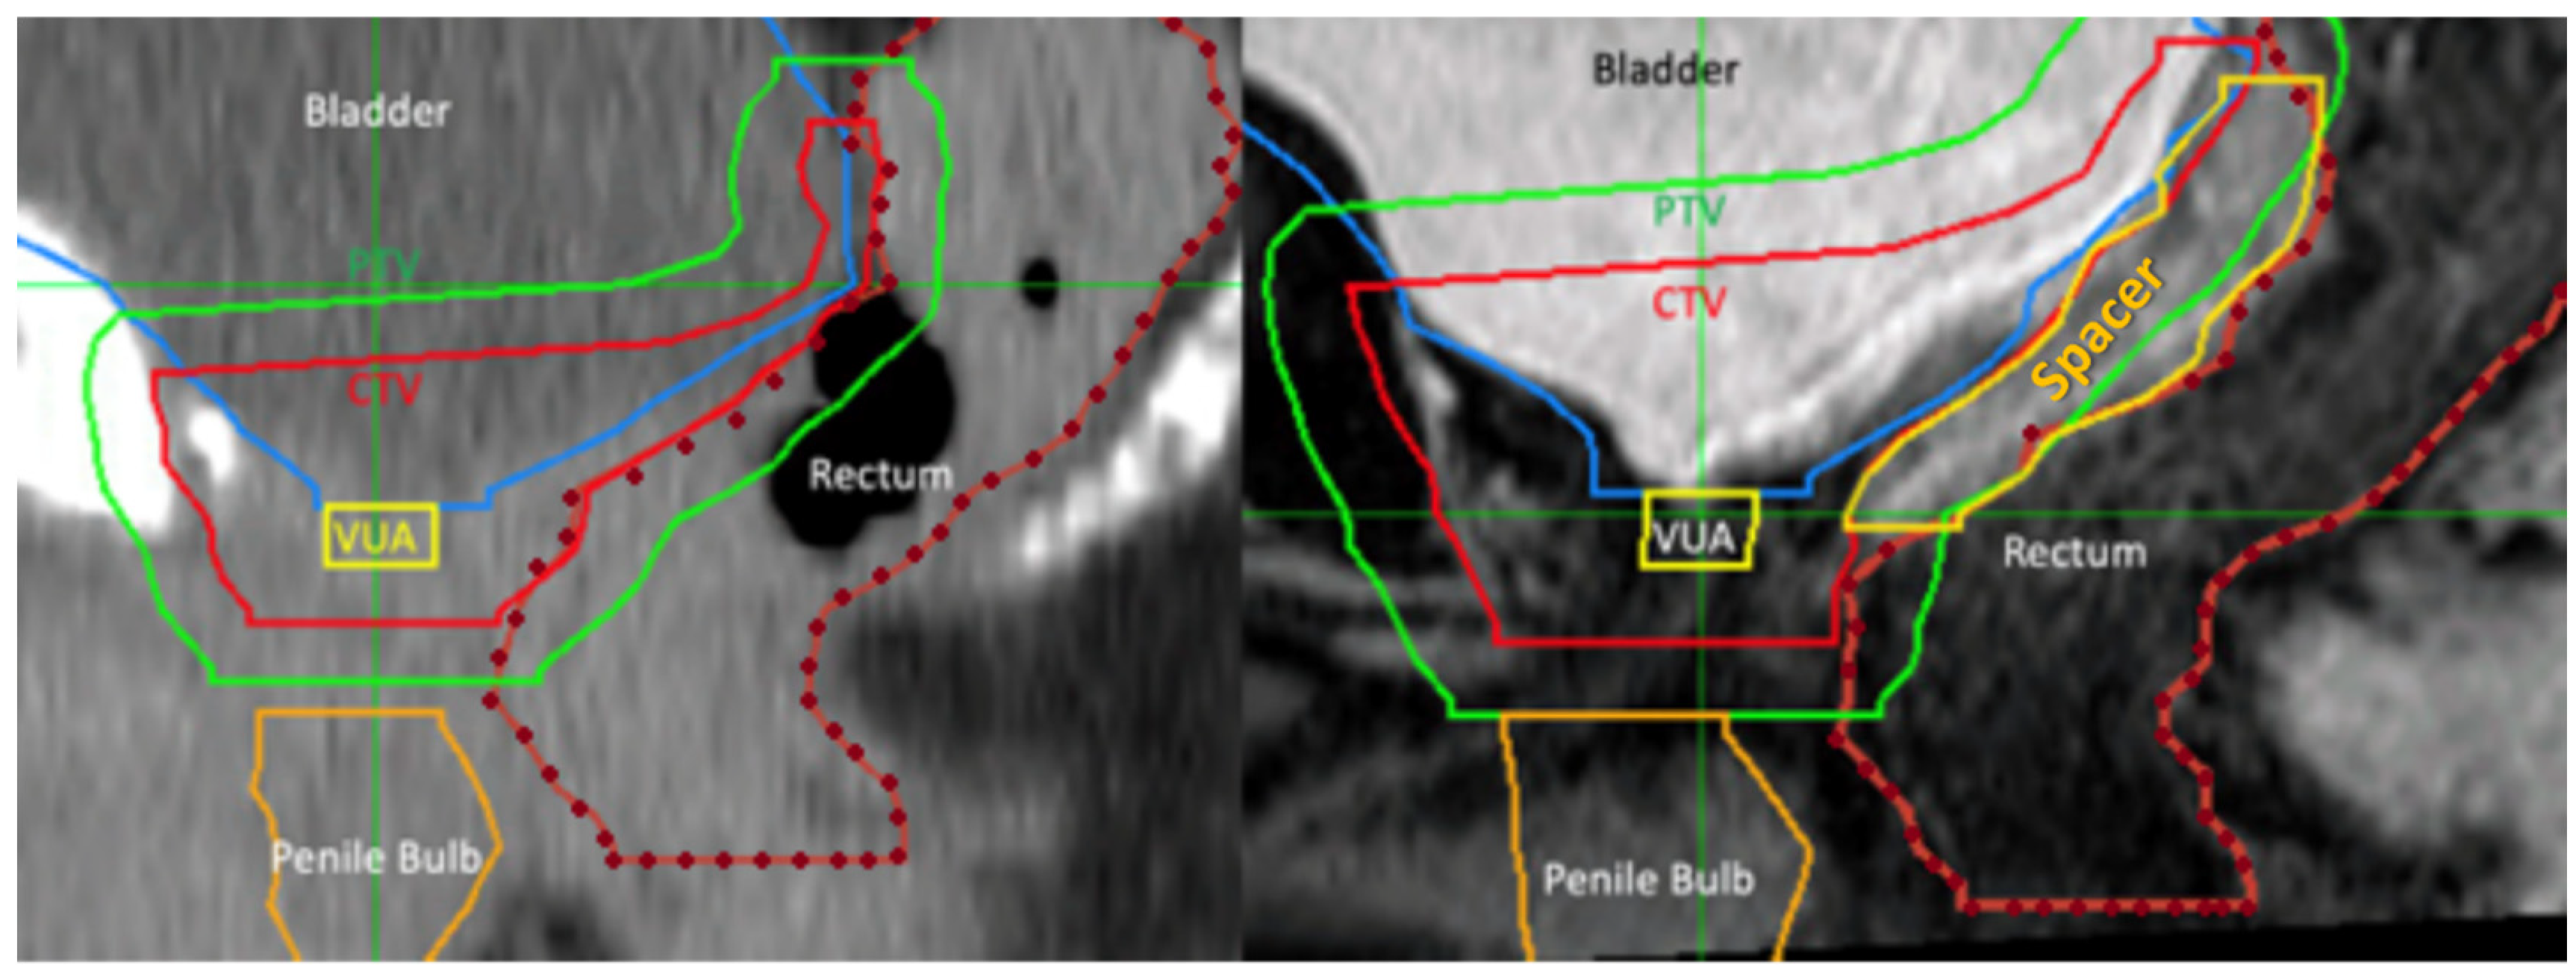

Patients underwent rectal spacing with either hyaluronic acid (Barrigel®, Palette Life Sciences, Santa Barbara, CA, USA) or hydrogel (SpaceOAR®, Boston Scientific, Massachusetts, Marlborough, MA, USA). The insertion technique is demonstrated in Figure 1. The rectal spacer was inserted into the perirectal fat posterior to the retained Denonvillier’s fascia between the bladder and anterior rectal wall using a transperineal approach under TRUS guidance. An indwelling urinary catheter was inserted to help delineate the vesico-urethral anastomosis (VUA). The perirectal fat was identified between the bladder and anterior rectum. An 18G spinal needle (Quincke Type Point® Spinal Needle, BD, Stockholm, Sweden) was inserted using a freehand technique targeting the midline of the prostate bed under sagittal TRUS guidance. Hydrodissection of the perirectal fat in the sagittal midline with 3 to 5 mL of sterile saline was attempted and, if successful, followed by insertion of 6 to 9 mL of hyaluronic acid (66% of cases) or hydrogel. After insertion, the vesico-rectal separation was calculated by measurement at the midline of spacer’s sagittal length. Pre- and post-spacer insertion images can be seen in Figure 2.

Figure 1.

Ultrasound image demonstrating the insertion of needle to the level of the vesico-ureteric anastomosis and just prior to hydrodissection and its relationship to the rectum and bladder neck (as outlined by the catheter balloon). Inset: transperineal approach for insertion of rectal spacer; here, the syringe contains normal saline ready for hydrodissection.